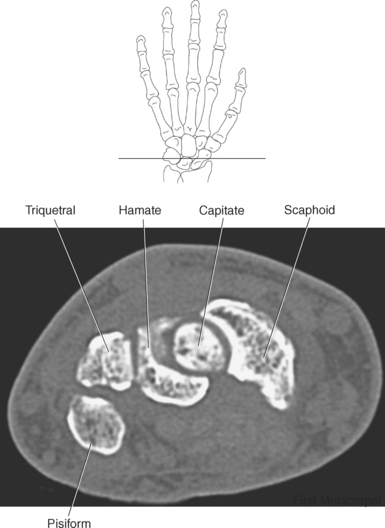

The bony anatomy of the wrist and hand consists of the distal radius and ulna, 8 carpal bones, 5 metacarpals, and 14 phalanges (Figure 9.101). Both the distal radius and ulna have a conical styloid process that acts as an attachment site for ligaments. The radial styloid process is located on the lateral surface of the radius, whereas the ulnar styloid process is located on the posteromedial side of the ulna. The carpal bones are arranged in proximal and distal rows. Located in the proximal row of carpal bones are the scaphoid (navicular), lunate (semilunar), triquetral (triquetrum), and pisiform bones. The pisiform is considered a sesamoid bone that is embedded in the tendon of the flexor carpi ulnaris. The distal row consists of the trapezium (greater multangular), trapezoid (lesser multangular), capitate (os magnum), and hamate (unciform) bones (Figures 9.102 through 9.114). The five metacarpals are small tubular bones with a proximal end (base), distal end (head), and shaft (body). The 14 phalanges that make up the fingers are short tubular bones. Like the metacarpals, each phalanx consists of a proximal (base), middle (body or diaphysis), and distal (head) portion. Each digit consists of 3 phalanges (proximal, middle, and distal), except for the thumb (first digit), which has only 2 phalanges (proximal and distal). The articulation of the phalanges of the second through fifth digits creates three interphalangeal joints: the metacarpophalangeal (MCP) joints classified as condyloid joints, proximal interphalangeal (PIP), and distal interphalangeal (DIP). The proximal and distal interphalangeal joints are classified as hinge joints (Figure 9.101). The first digit, which consists of 2 phalanges, has just two joints: the MCP joint, classified as a saddle joint, and an interphalangeal joint, classified as a hinge joint (Figure 9.101).

Figure 9.116 Coronal, T1-weighted MR scan of wrist with triangular fibrocartilage complex.

Key: t, Triquetrum; TFCC, triangular fibrocartilage complex; u, ulna; r, radius; s, scaphoid; l, lunate; H, hamate; C, capitate; Td, trapezoid; Tm, trapezium; P, pisiform; L, lunate; S, scaphoid; LT, Lister’s tubercle.